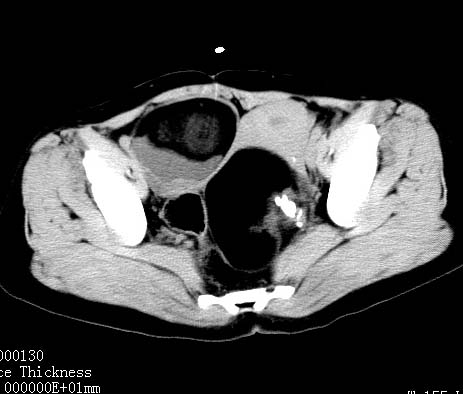

女性 病人 44岁 盆腔 下腹部痛1天!

盆腔内低密度为主混杂等密度及少许囊样与班状钙化影,如果做了肠道准备就好了。支持畸胎瘤。当然做mri会更好

典型的双侧附件畸胎瘤.

支持各位大侠观点.病人有急性腹痛,需除外有扭转可能.建议mri.

盆腔多发畸胎瘤,较为典型。